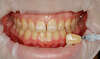

Vos dents présentent une teinte qui vous semble trop foncée

Après quelques jours de procédure vos dents retrouveront une teinte plus agréable.

La procédure consiste à appliquer un gel sur les dents grâce une gouttière souple